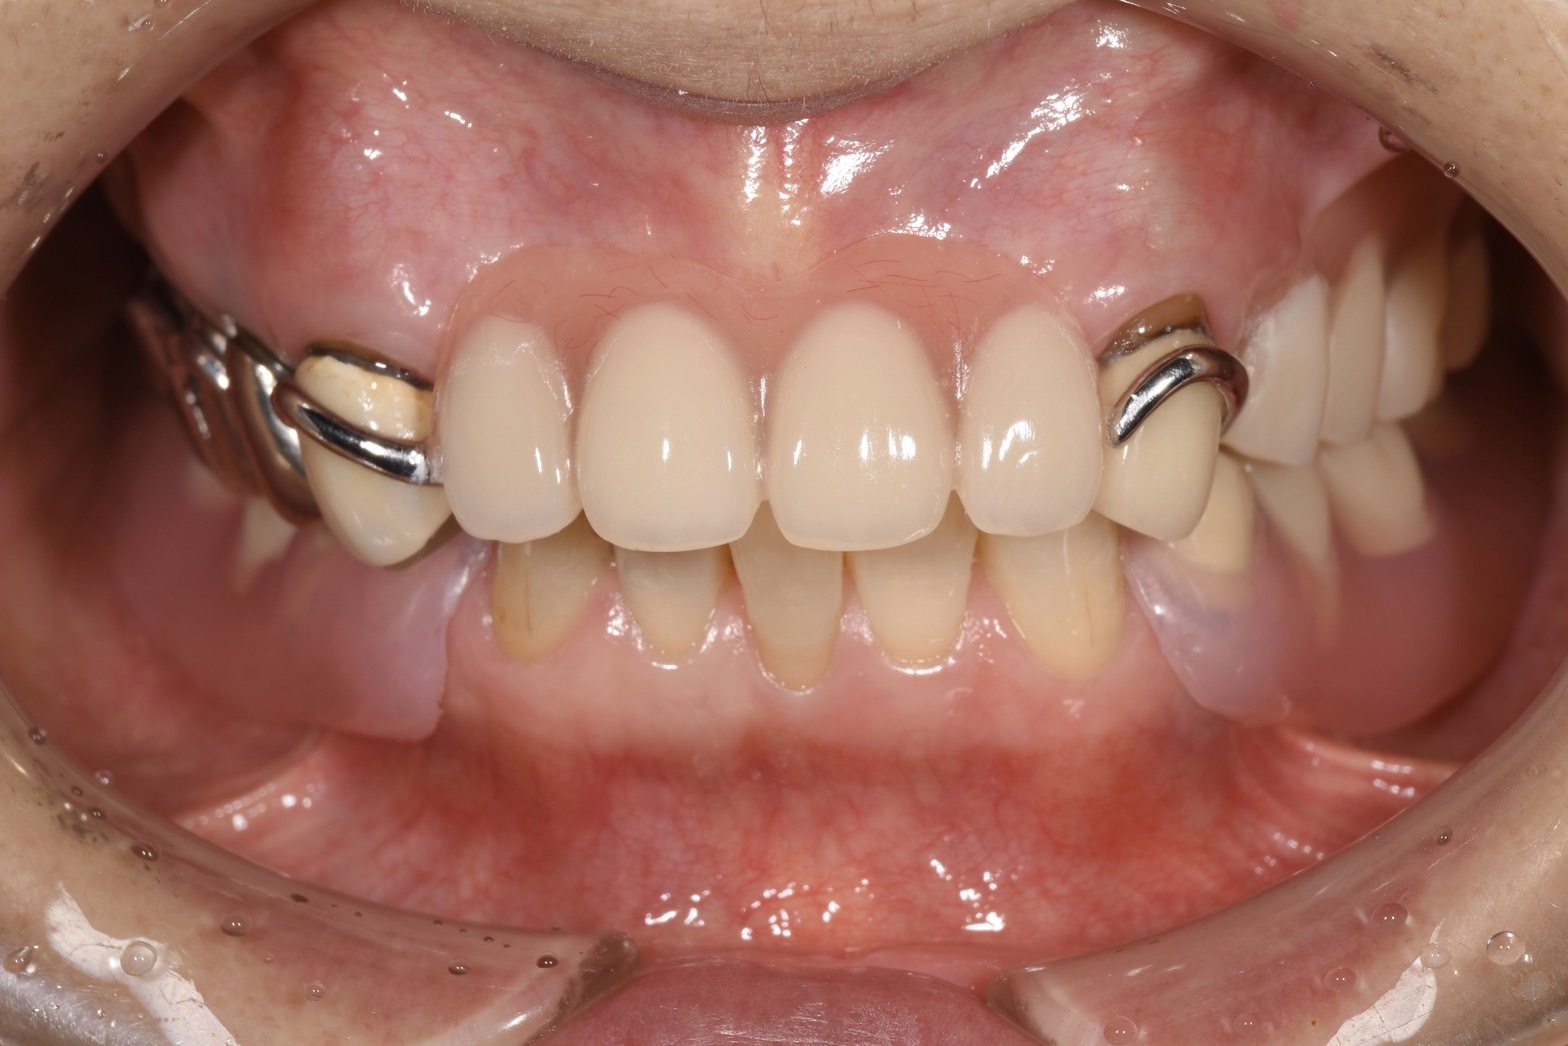

• ノンクラスプデンチャー

ノンクラスプデンチャー